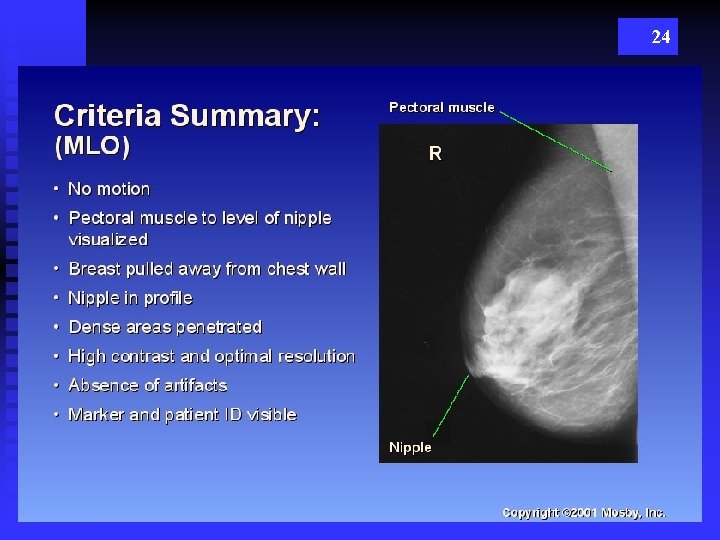

23

24